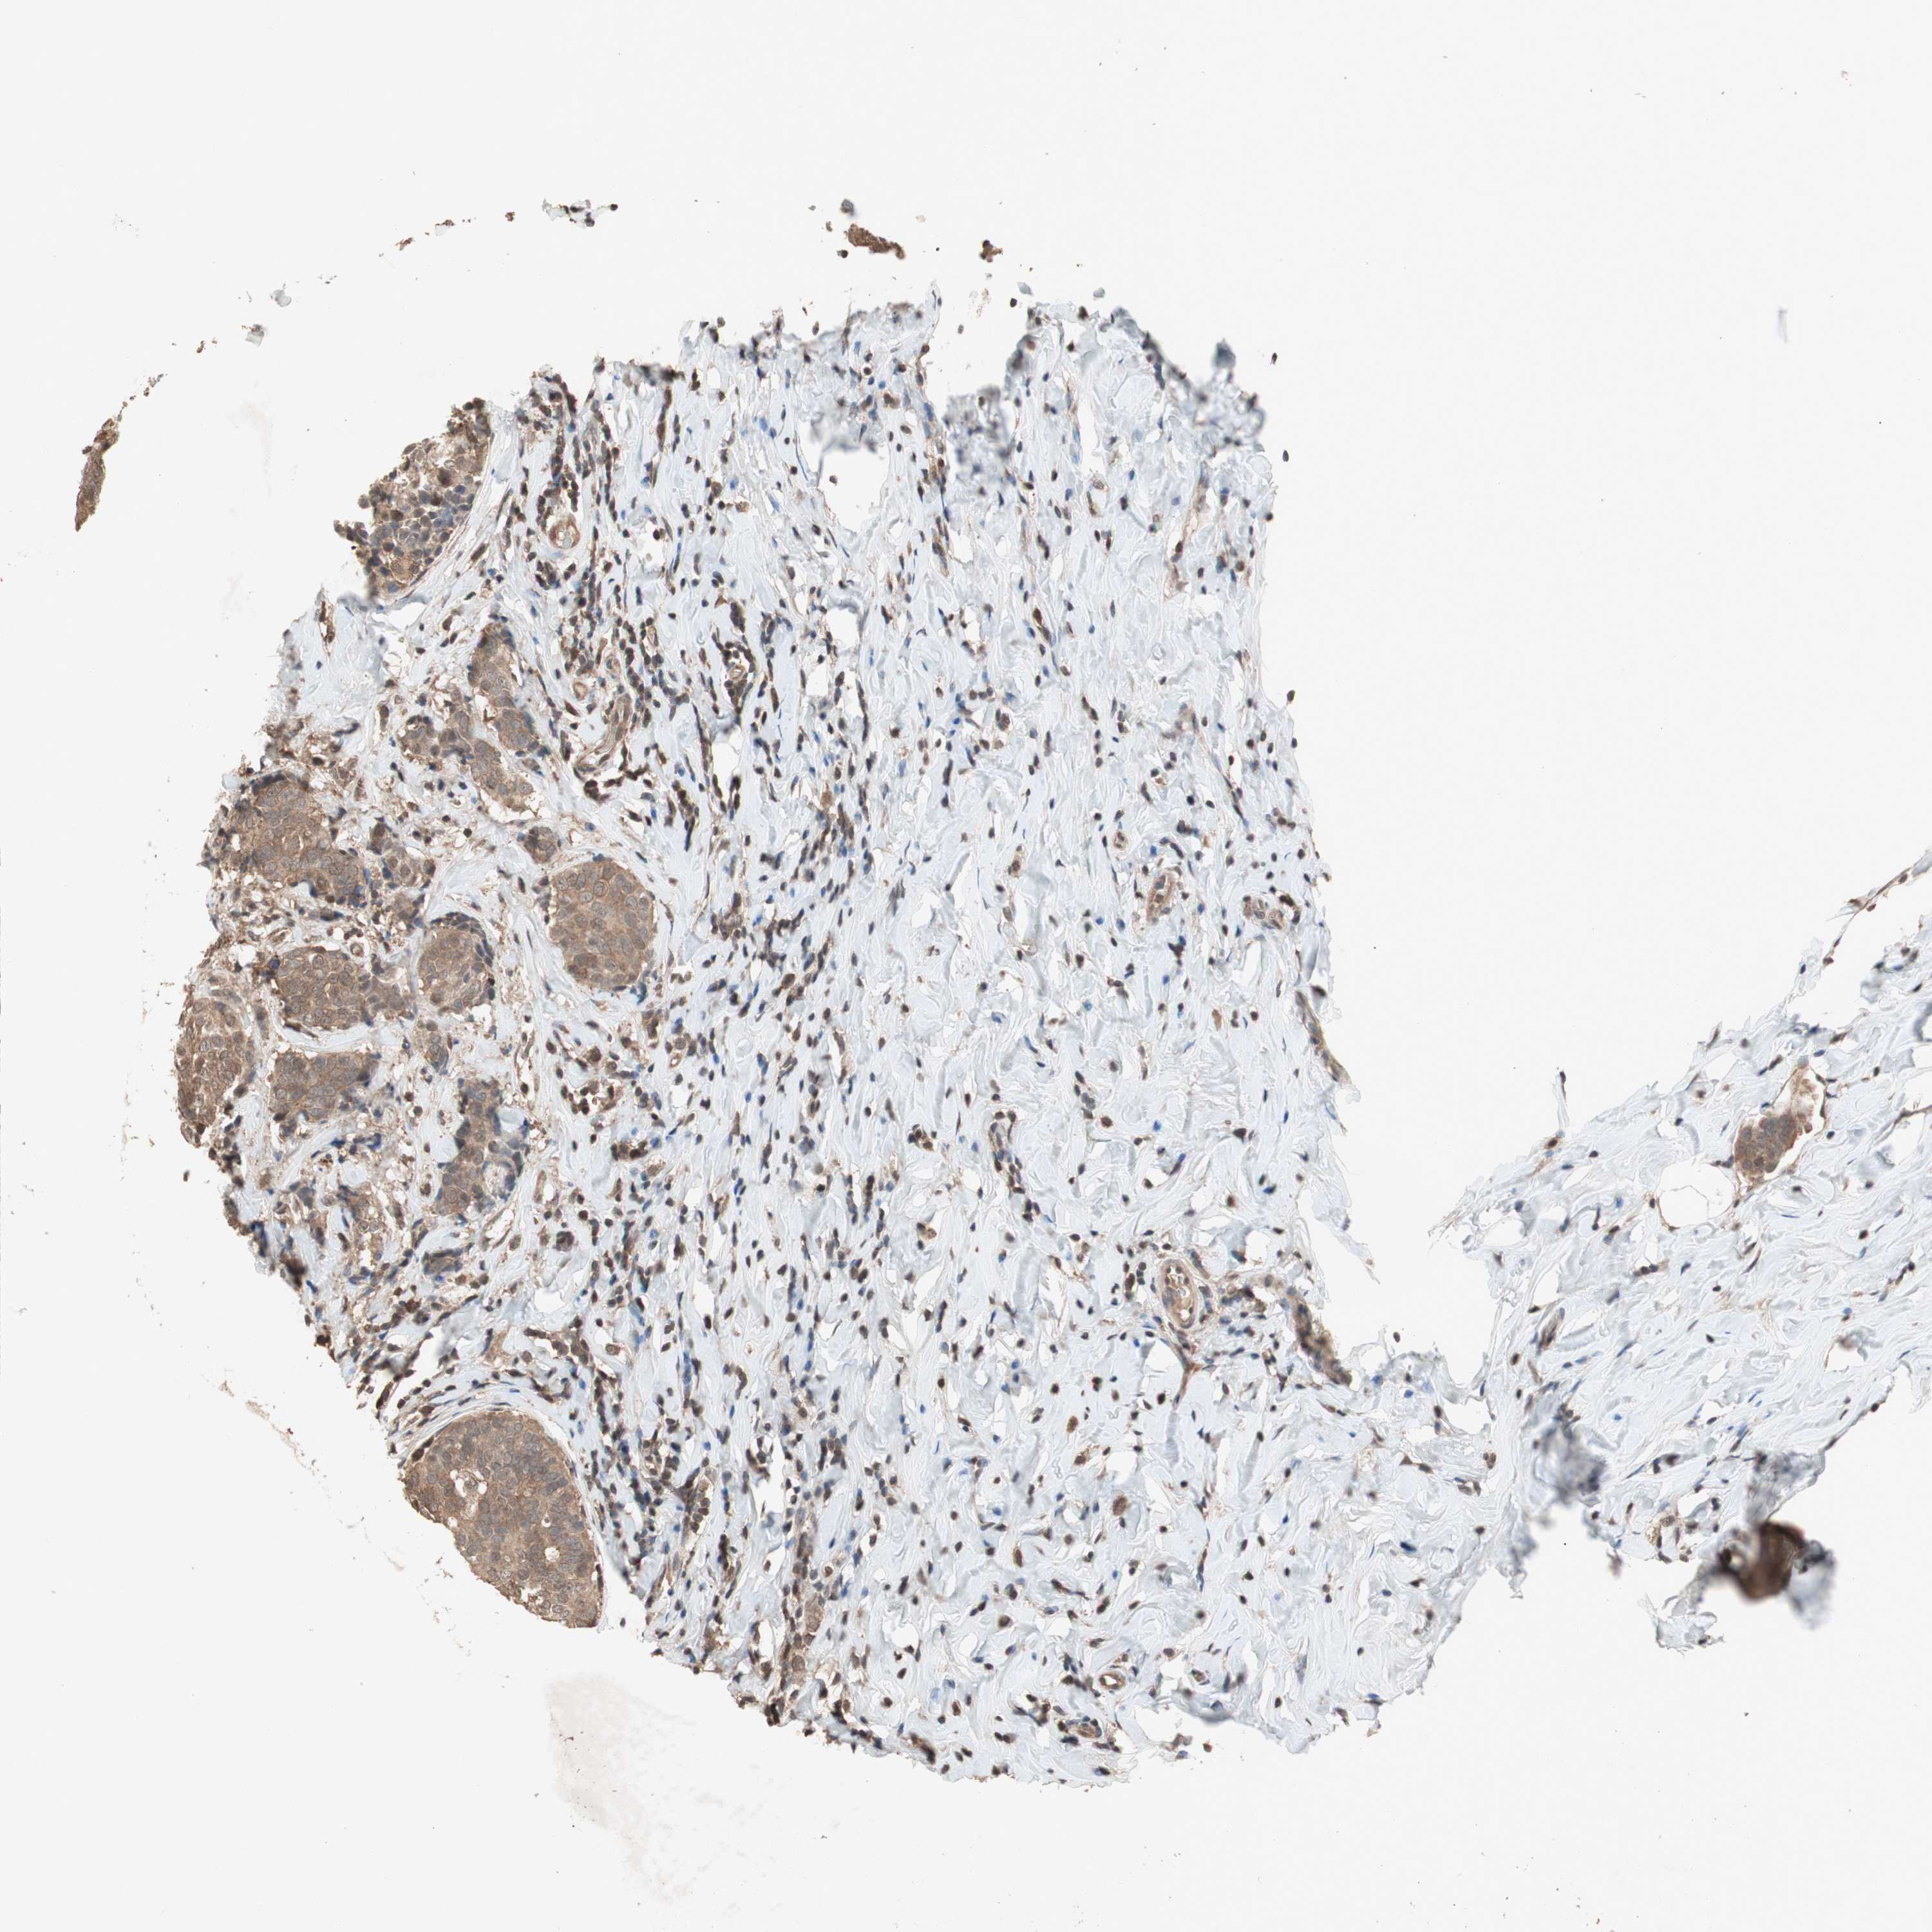

CANCER BREAST CANCER Show tissue menu

Breast cancer

Human cancer